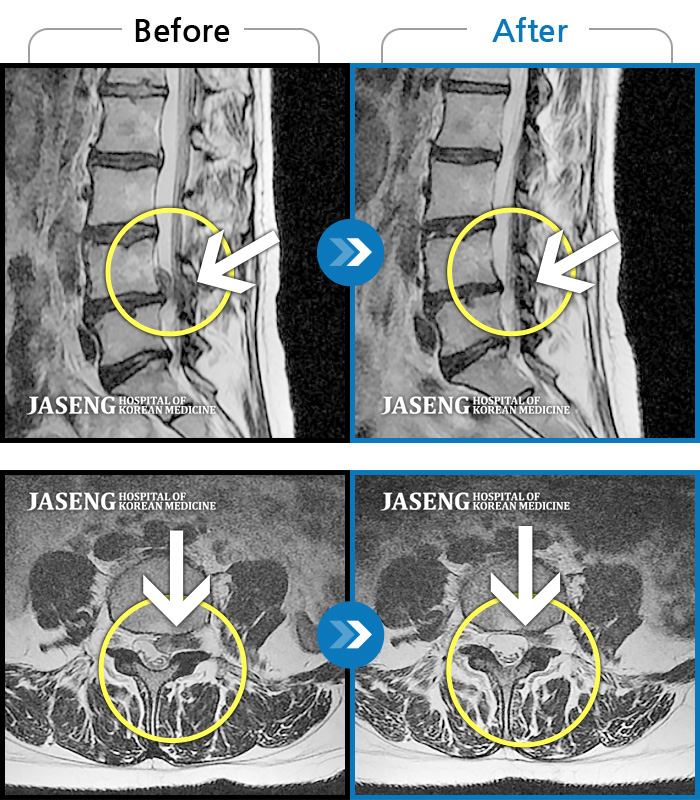

MRI 치료사례

허리통증과 좌측 하지방사통